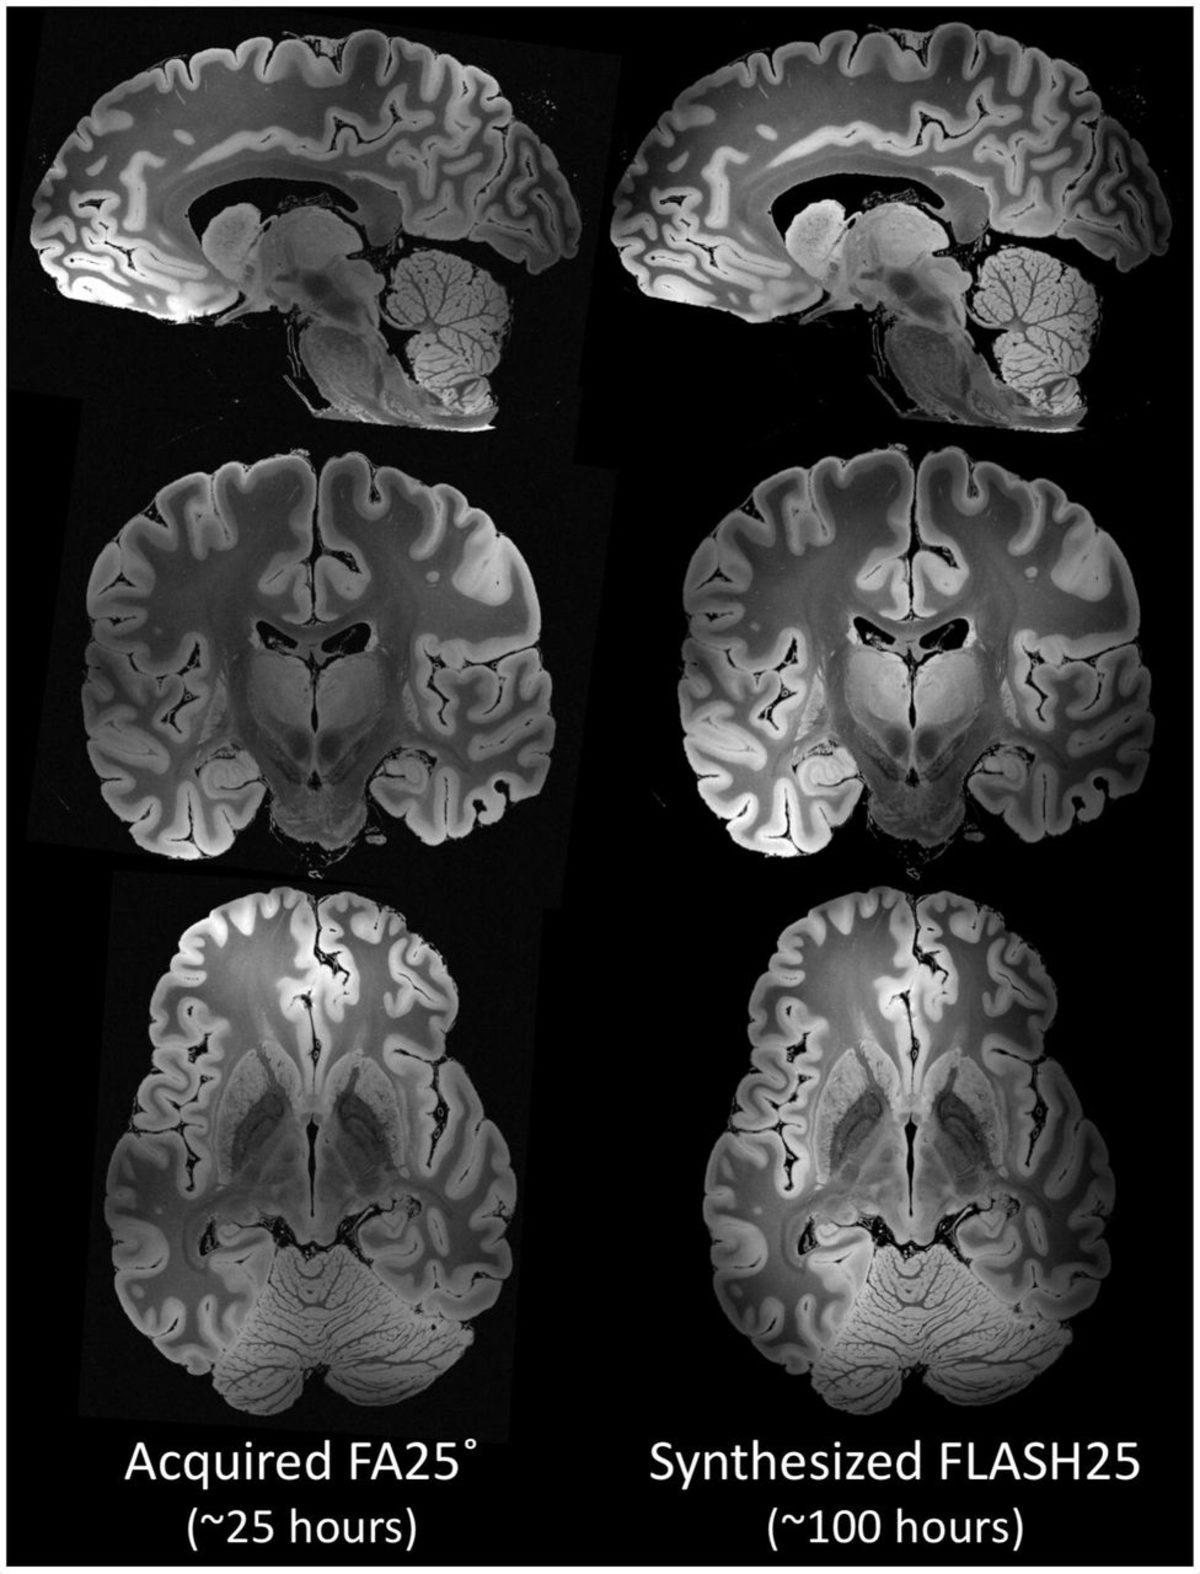

100 saatten fazla süren bir MR taraması, tüm insan beyninin daha önce eşi benzeri görülmemiş derecede ayrıntılı bir görüntüsünü gözler önüne serdi. Massachusetts General Hospital araştırmacıları tarafından yapılan bu çalışmada, 58 yaşında bir kadına ait olan ve bilim için bağışlanmış bir beyni taramak için yakın zamanda FDA tarafından onaylanan ‘7 Tesla MRI’ adındaki MR cihazı kullanıldı. Bu taramadan sonra ortaya çıkan MR görüntüleri ise insan beynini 0,1 milimetreye kadar detaylı bir şekilde gösteriyor.

Science News’te yayınlanan araştırmaya göre beyin taraması başlamadan önce araştırmacılar, beynin hareketsiz durmasını sağlayan ve hava kabarcıklarının ortadan kaybolmasına izin veren özel bir ortam hazırladılar. Taranmaya hazır hâle getirilen beyin, daha sonra ‘7 Tesla MRI’ cihazıyla neredeyse 5 gün boyunca tarandı ve inanılmaz yüksek çözünürlüklü ve üç boyutlu bir beyin MR’ı ortaya çıktı.